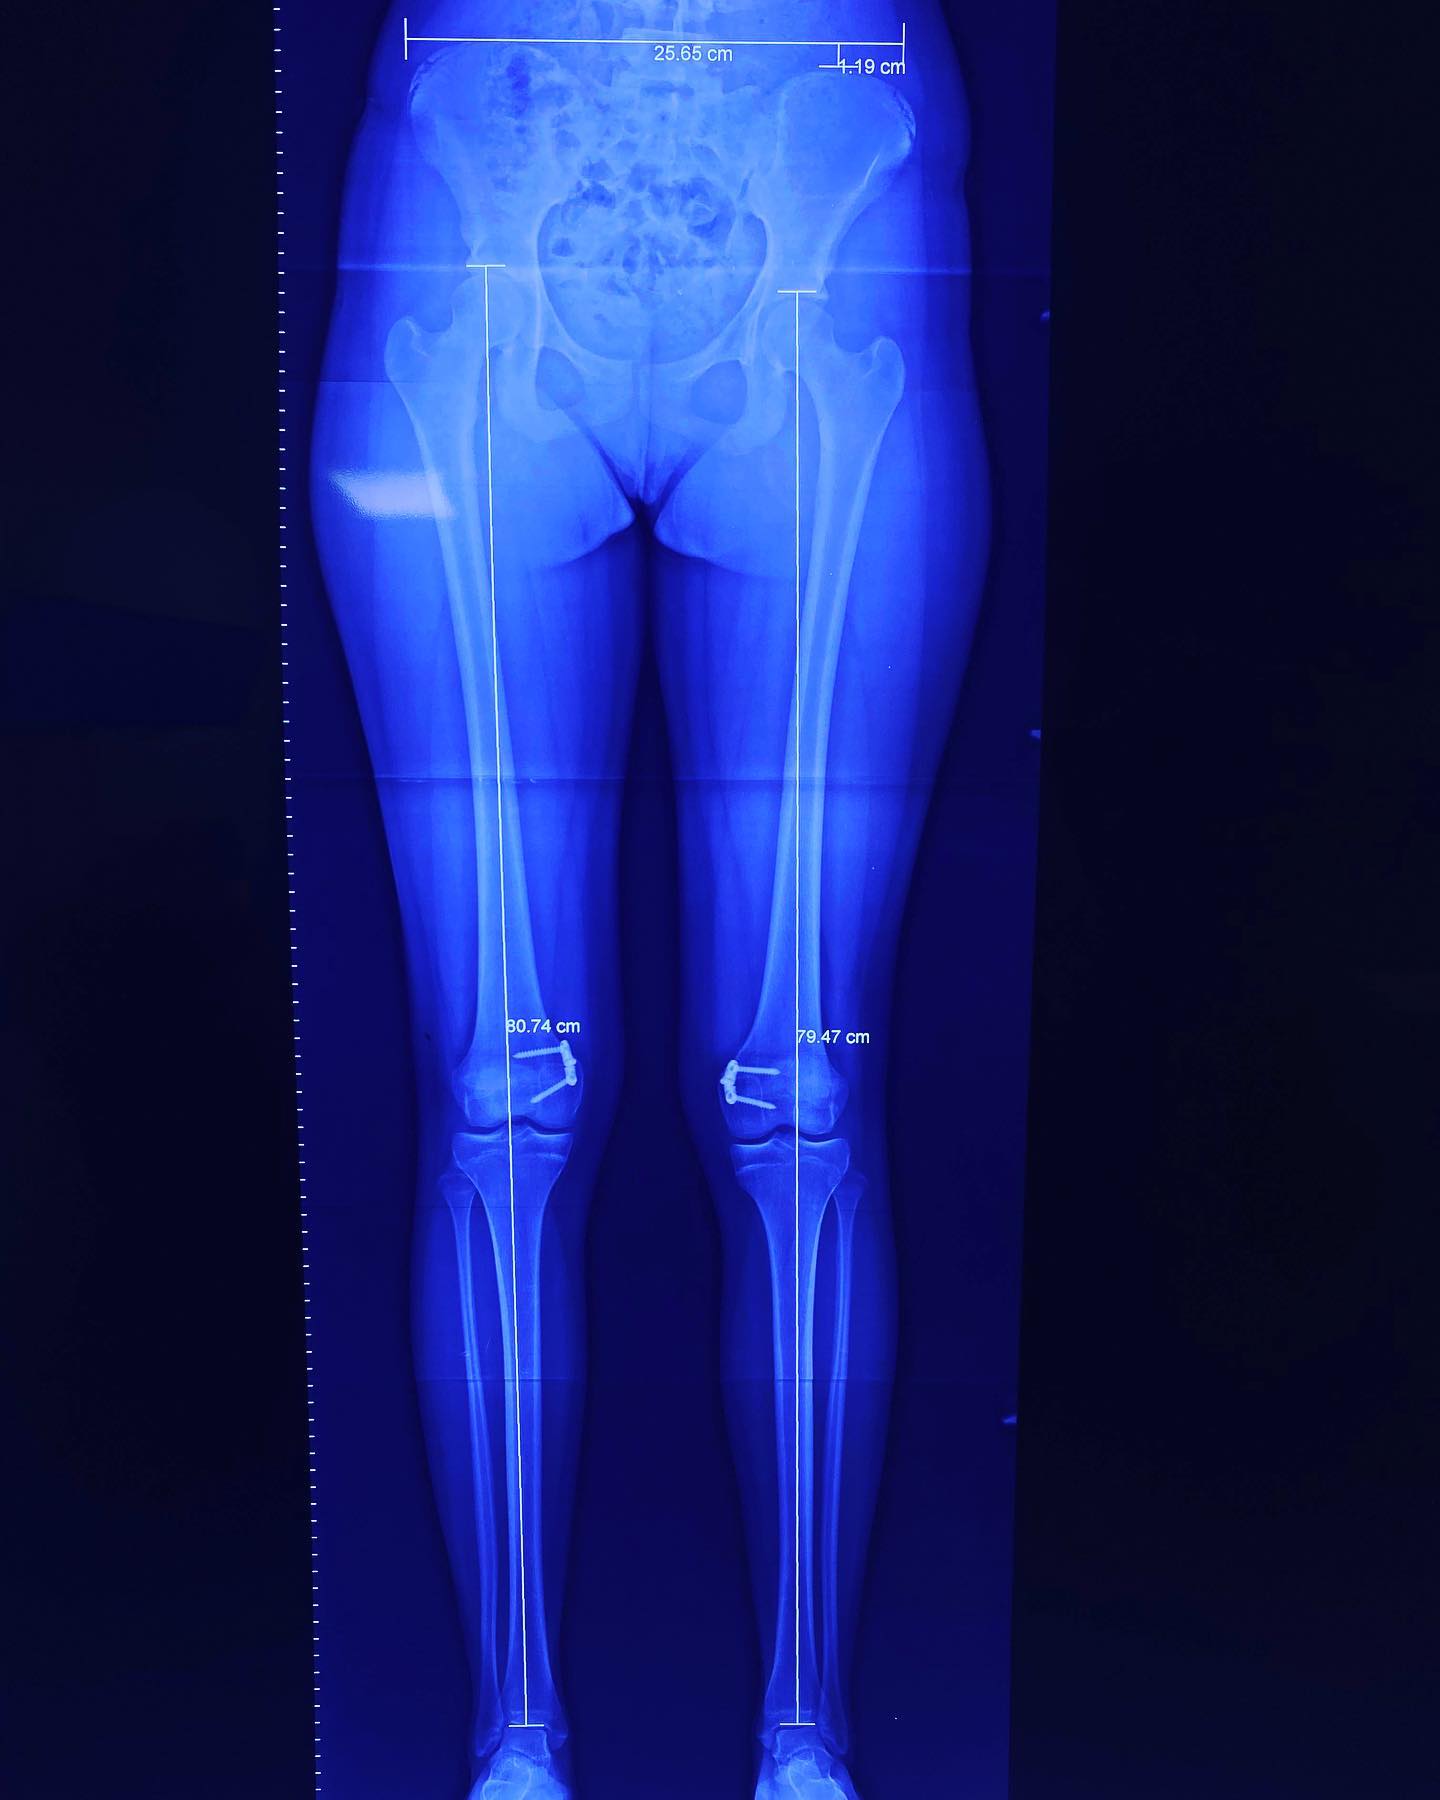

• Discrepancias de longitud en miembros pélvicos

También llamadas rodillas valgas o rodillas en varo, estas condiciones se refieren a la alineación de las piernas. Estas alineaciones pueden ser un estado natural del desarrollo de un niño o una niña hasta los 7 años de edad. Después de esta edad, ya no se consideran normales. Sin embargo, en algunos casos, esta deformidad puede aumentar hasta llegar a ser discapacitante y dolorosa, y es en ese momento cuando debe ser tratada.